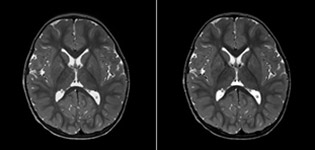

Le marquage des spins artériels pseudo-continu (pCASL) a été développé pour l’imagerie de perfusion cérébrale sans agent de contraste. “C’est vraiment intéressant pour les patients en pédiatrie, où la tendance générale est de limiter l’administration de produits de contraste”, explique le Dr Miller. Accroître la confiance dans des applications spécifiques “Nous avons renforcé notre confiance à l’égard du pCASL en le comparant à l’imagerie de perfusion de contraste. Une fois que nous étions sûrs qu’il représentait ce que les perfusions de contraste représentaient, nous avons amélioré la fiabilité de nos diagnostics par l’imagerie en série de la phase aiguë ou des phases à long terme chez plusieurs patients atteints d’anomalies artérielles.

“En association avec l’imagerie de diffusion pondérée, il aide à évaluer plus en détail le degré d’anomalie de perfusion chez un patient souffrant d’une ischémie aiguë. Plusieurs de nos patients souffrent d’insuffisance artérielle chronique à cause d’anciennes anomalies artérielles ou d’anomalies artérielles acquises telles que la drépanocytose ou la neurofibromatose. Parfois, la première manifestation de la progression de la maladie chez l’enfant est une réduction dans la perfusion cérébrale avant que les symptômes de l’AVC ne se manifestent cliniquement ou une réduction dans l’imagerie de diffusion pondérée. Nous utilisons le pCASL pour aider à définir l’anomalie de perfusion.”

Je recommanderais également aux autres nouveaux utilisateurs de commencer à interpréter les images pCASL par rapport aux autres images standard, T2, FLAIR et DWI, jusqu’à ce qu’ils puissent interpréter ces images par eux-mêmes en toute confiance.” “L’utilisation du pCASL est efficace chez les patients présentant une sténose cérébrovasculaire chronique, pour laquelle les cliniciens ont besoin d’informations sur la façon dont les mécanismes compensatoires du cerveau fonctionnent pour permettre la perfusion cérébrale. Souvent, les cliniciens prennent en compte la façon dont les mécanismes compensatoires apparaissent pour pouvoir administrer la perfusion adéquate au cerveau du patient. Ils peuvent également intervenir chirurgicalement ou prendre d’autres décisions de prise en charge.” “Une autre application spéciale est l’évaluation de la réactivité cérébrovasculaire avec un examen de perfusion Diamox, lors duquel on soustrait deux ensembles d’images pCASL.”